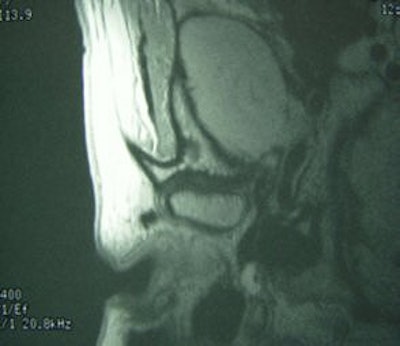

![]() |

Same patient. Postop lateral displacement of right disk. Pain improved in both joints; clicking resolved in left joint only. Images courtesy of Dr. Jessica Lee.